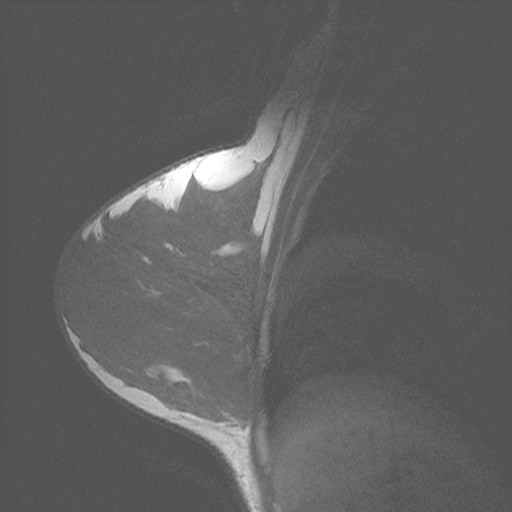

borst